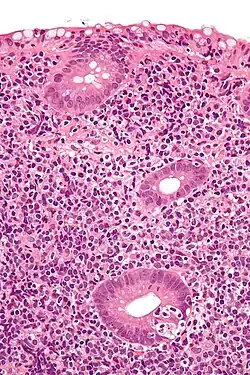

Micrograph showing a lymphoepithelial lesion (lower right of image) in a primary gastrointestinal tract lymphoma. H&E stain.

In pathology, lymphoepithelial lesion refers to a discrete abnormality that consists of lymphoid cells and epithelium, which may or may not be benign.

It may refer to a benign lymphoepithelial lesion of the parotid gland or benign lymphoepithelial lesion of the lacrimal gland, or may refer to the infiltration of malignant lymphoid cells into epithelium, in the context of primary gastrointestinal lymphoma.[1]

In the context of GI tract lymphoma, it is most often associated with MALT lymphomas.[1]